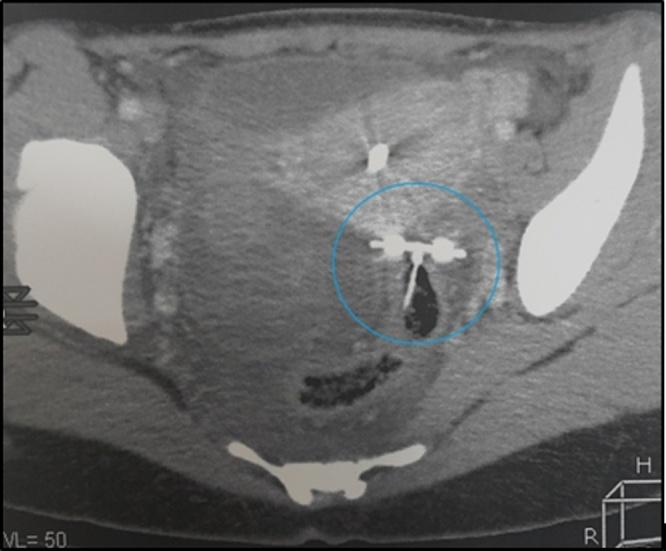

We report a case of a 26-year woman, carrying an IUD for 2 years, who presented to the emergency with pelvic pain with breakthrough bleeding. Abdominal imaging revealed the presence of two devices the first of which was located in the uterine cavity and the other in the wall of the sigmoid colon associated with a 5-centimeter pelvic collection. Intraoperatively, the IUD was found to be embedded in the wall of the sigmoid colon which was removed by wedge resection of the involved segment followed by a closure of the puncture with drainage.

我们报告一例26岁女性,放置宫内节育器2年,因突破性出血伴盆腔疼痛前来急诊。腹部影像学检查发现有两个节育器,其中一个位于子宫腔内,另一个位于乙状结肠壁,伴有5厘米的盆腔积液。术中发现宫内节育器嵌入乙状结肠壁,通过楔形切除受累肠段并缝合穿刺口并引流将其取出。